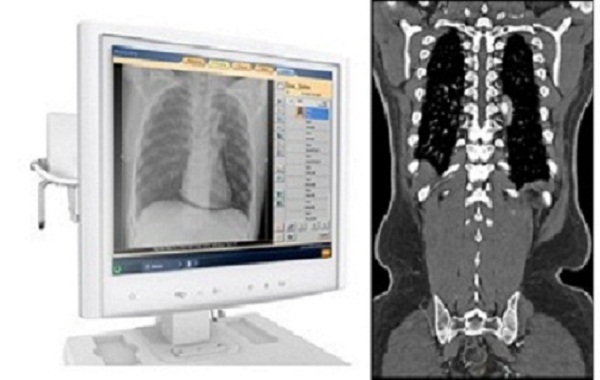

في الولايات المتحدة، ازداد استخدام التصوير المقطعي المحوسب إلى 3 أضعاف تقريبًا، لينتقل بذلك من 52 عملية تصوير لكل 1000 مريض إلى 149 عملية تصوير لكل 1000 مريض بين 1996 و2010. ووفقًا للكلية الأمريكية للأشعة (ACR)، يتم إجراء 68 مليون عملية تصوير مقطعي محوسب سنويًا في الولايات المتحدة حاليًا. وبعبارة أخرى، سيتلقى أمريكي واحد تقريبًا من كل 5 أمريكيين تصويرًا مقطعيًا محوسبًا هذا العام. والسبب بسيط؛ فالتصوير المقطعي المحوسب يقدم صورة أفضل وأكثر دقة مقارنة بالأشعة السينية القياسية، وقد يلغي أيضًا هذا التصوير الحاجة إلى الجراحة الاستكشافية في بعض الحالات. وهذه الفائدة هي الجزء الأول من المعادلة.

تُعد جرعة الإشعاع الجزء الآخر من المعادلة. فبواسطة عمليات التصوير المقطعي المحوسب، يمكن للفنيون حماية أنفسهم أو الحدّ من التعرّض لجرعات الإشعاع من خلال الخروج من الغرفة أو الوقوف خلف حاجز أثناء الإجراء. إلا أن المرضى الذين يخضعون إلى العلاج فهم يتعرضون إلى الإشعاعات. ولكن، على الرغم من أن التصوير المقطعي المحوسب يزيد من الأعباء التي تتسبّب بها الجرعة الإشعاعية، دعونا نناقش هذه التقنية بكل موضوعية. إن كمية إشعاع "الخلفية" الذي نتعرض له جميعًا سنويًا هو بالفعل أعلى في المتوسط من بعض عمليات مسح التصوير المقطعي المحوسب. ألق نظرة على هذا الرسم البياني: